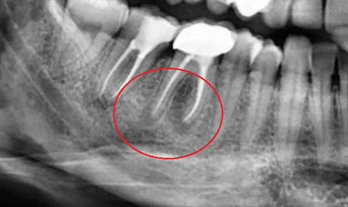

The dental professional will first examine the teeth and gums to check for any signs of dental problems, such as cavities, gum disease, or other oral health issues.

Scaling

The dental professional will use a specialised instrument to remove plaque and tartar from the teeth and gums. This process is known as scaling and is typically done with ultrasonic or hand-held instruments.

• Accurate diagnosis of dental problems with state-of-the-art technology, digital X-rays and intraoral cameras.